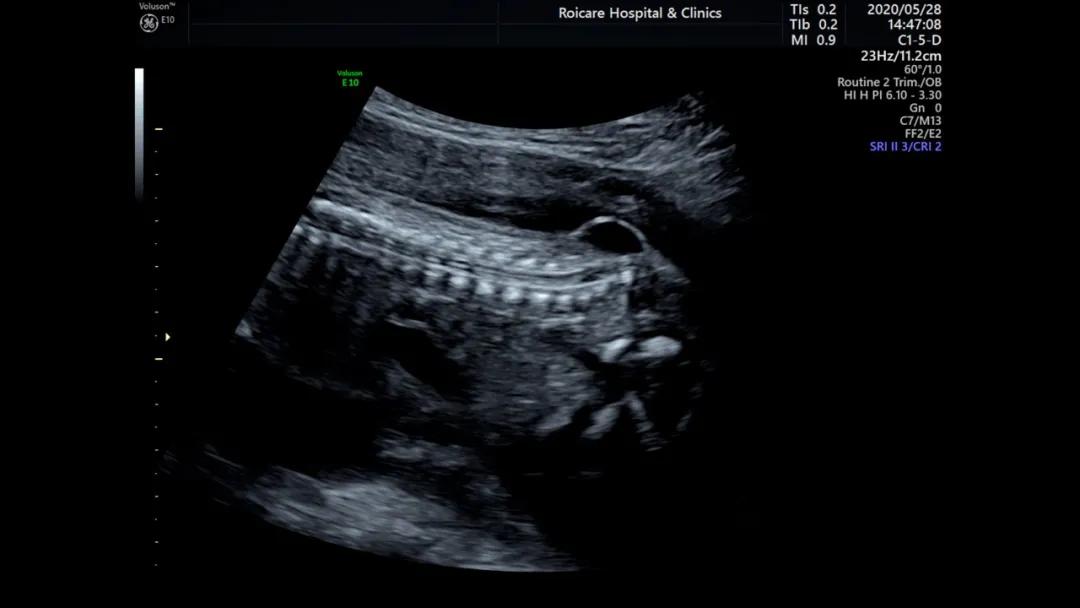

骶尾部脊柱裂伴脊髓脊膜膨出

闭合性脊柱裂受累段脊髓神经损伤常较轻,新生儿和婴幼儿症状不明显,随着年龄增长,脊髓圆锥及马尾和椎管后壁粘连,脊髓圆锥不能随发育向头侧移位,被粘连部位或者异常神经终丝牵拉缺血,导致脊髓栓系综合征。闭合性脊柱裂也可无任何临床症状。